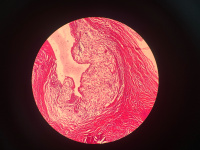

尺神经外膜囊肿

右手环小指麻木肌肉萎缩三月,肌电图示:右肘管尺神经损害,右肘x线:右肘骨性关节炎

尺神经外膜串珠样囊肿

灰白囊皮组织一块:总大小1.8*0.5*0.3厘米,囊壁厚0.3厘米,取囊壁

是腱鞘囊肿吗?请老师们指点